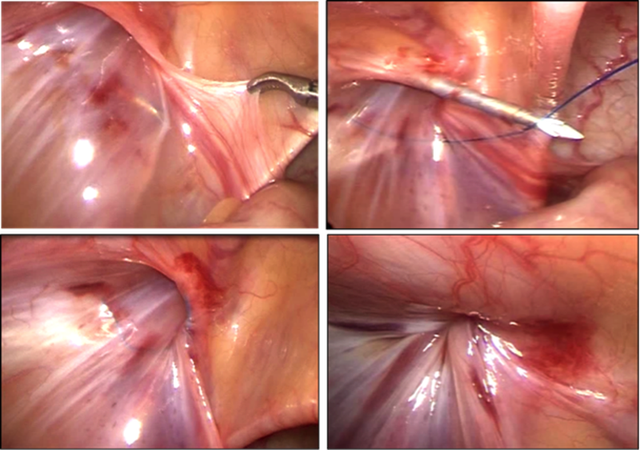

Cho đến nay phẫu thuật là phương pháp điều trị duy nhất để điều trị bệnh lý này. Phẫu thuật có thể là phẫu thuật mổ mở kinh điển hoặc phẫu thuật nội soi 1 lỗ, 2 lỗ hoặc 3 lỗ.

Tuy nhiên, hiện nay phẫu thuật nội soi được lựa chọn nhiều, ưu điểm của phương pháp phẫu thuật mới này là đường mổ nhỏ, ít đau sau mổ, có thể dễ dàng phát hiện thoát vị bên đối diện nếu có và xử lý luôn trong 1 lần mổ, điều này đặc biệt quan trọng đối với thoát vị bẹn ở trẻ sơ sinh - lứa tuổi có khả năng cao bị cả hai bên.